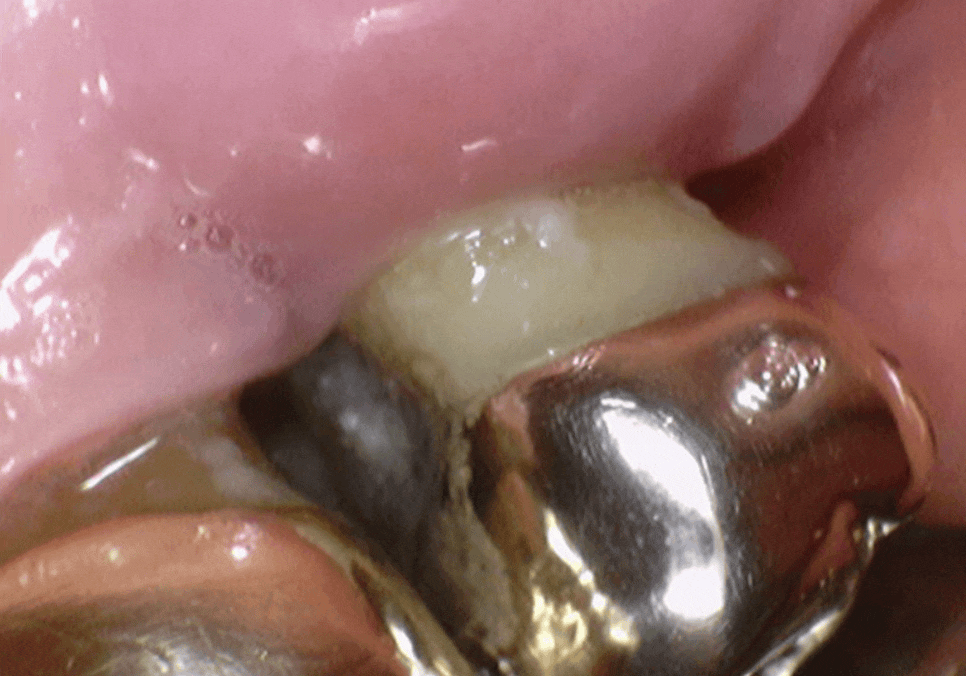

얼마 전 오른쪽 위 어금니가

심하게 흔들린다며 한 환자분이 내원하셨어요.

입안을 살펴보니 예전 금니 아래로

잇몸이 쑥 내려가 뿌리가 훤히 드러나 있었고,

잇몸은 이미 붉게 부어있는 상태였죠.

잇몸이 내려가다 보니 치아 사이 빈 공간으로

음식물이 가득 끼어있었는데,,

치아 사이는 칫솔이 잘 닿지 않아

남은 음식물이 잇몸을 더 빠르게 녹이고 있었습니다.